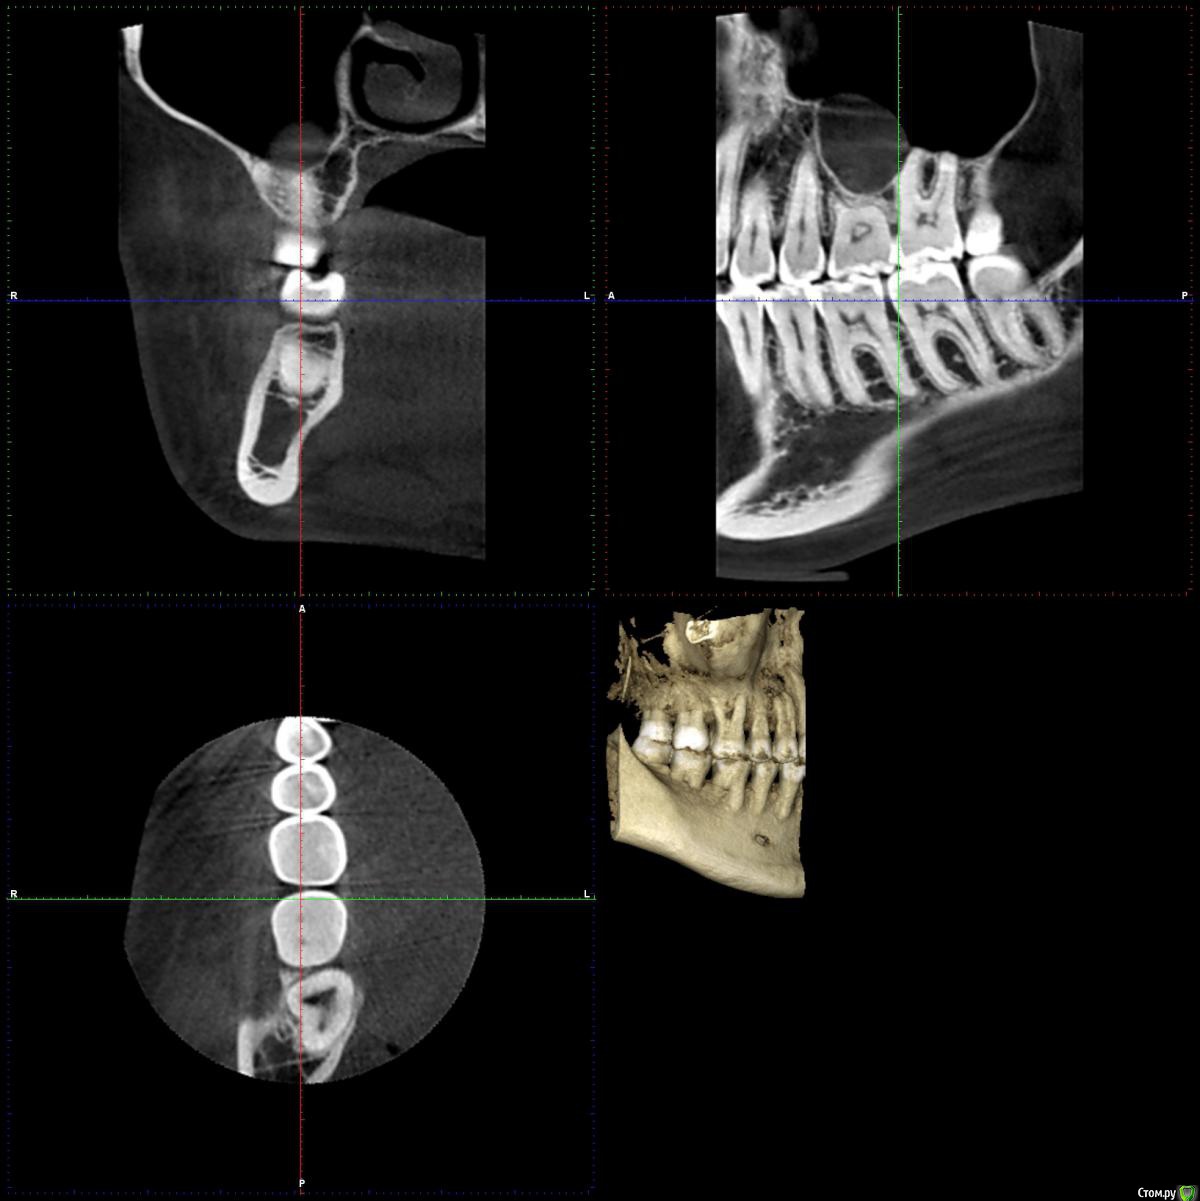

chuvashova_mv Опубликовано 18 июня, 2016 Поделиться Опубликовано 18 июня, 2016 (изменено) Мне 31 год. Тюмень. Сильное оголение корней каждого зуба. Сосочки на месте. Карманов нет. Тонкий биотип десны. Была у неск.ортодонтов, дело не в прикусе.Эндокринолог значит.отклонений не видит (щитовидка в норме, сах.диабета нет, менстр.регулярная сейчас, раньше были сбои), только имт 16,5. Есть ребёнок 3 года, заберем. сама.Гастроэнтеролог - хр.гастродуоденит со школы, желудок работает не в полную меру.Неврология - всд по гипотония.типу., бруксизма нет.Очень сух.кожа с рождения, особенно тяжко зимой.Прилагаются кт и оптг.Вопрос: все очень плохо? У нас в городе вызвались только два врача оперировать, но таких случаев как у меня у них не было.Нужна помощь пародонтологов-хирургов, кто с таким сталкивался. Изменено 18 июня, 2016 пользователем chuvashova_mv Ссылка на комментарий

faity Опубликовано 20 июня, 2016 Поделиться Опубликовано 20 июня, 2016 Судя по ОПТГ дисфункция и деформация ВНЧС, гипертрофия жевательной мускулатуры слева.По фото множественные рецессии и патологическая стираемость зубов.У вас классическая окклюзионная травма которая дала рецессию, стираемость, щелчки в суставе(если уже появились). Вам гнатолог нужен для начала ибо у вас причину сложнее устранить чем последствия в виде стираемости и рецессий.Зубы сжимаете во сне или во время бодроствования? 2 Ссылка на комментарий